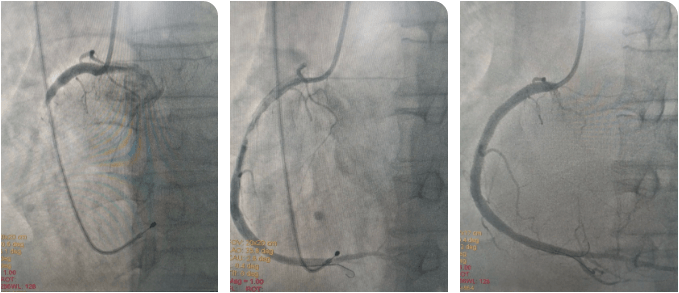

時(shí)間就是生命!心內(nèi)科介入團(tuán)隊(duì)與死神展開(kāi)較量,大家輪流為患者進(jìn)行心肺復(fù)蘇,并以最快的速度完成消毒、鋪巾?;颊叽髣?dòng)脈搏動(dòng)消失,李新國(guó)主任、吳利杰主任憑借扎實(shí)的基本功,盲穿腋靜脈及右側(cè)股動(dòng)脈,植入臨時(shí)起搏器。根據(jù)心電圖判斷罪犯血管為右冠狀動(dòng)脈,李新國(guó)主任果斷直接選擇右冠指引導(dǎo)管造影,造影證實(shí)判斷,右冠狀動(dòng)脈粗大,自近段完全閉塞。12:36介入團(tuán)隊(duì)將導(dǎo)絲送到了患者閉塞血管的遠(yuǎn)端,并用球囊對(duì)閉塞血管擴(kuò)張后順利恢復(fù)前向血流。奇跡出現(xiàn)了,患者微弱的心跳逐漸有力,血壓、心律也逐漸好轉(zhuǎn)。此時(shí)的患者仍處于昏迷狀態(tài),攜帶呼吸機(jī)及臨時(shí)起搏器轉(zhuǎn)入CCU病房繼續(xù)治療。

術(shù)后,在李新國(guó)主任、沈靖超主治醫(yī)師及段秋燕護(hù)士長(zhǎng)帶領(lǐng)的護(hù)理團(tuán)隊(duì)精心施治、細(xì)心護(hù)理下,患者于當(dāng)日意識(shí)轉(zhuǎn)清醒,拔除氣管插管,生命體征穩(wěn)定,之后也順利渡過(guò)心梗后心力衰竭、消化道應(yīng)激性潰瘍、肺部感染等并發(fā)癥,3天后拔除臨時(shí)起搏器,1周后于右冠狀動(dòng)脈動(dòng)脈植入2枚支架,之后轉(zhuǎn)入普通病區(qū)繼續(xù)鞏固治療,并于近期順利出院。